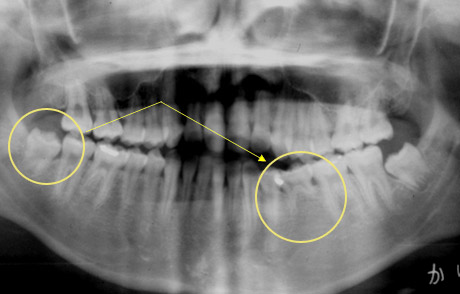

適切な条件がそろえば、歯の移植が可能です。歯の移植とは、治療することができない歯を抜いて、その場所へ本人の親知らずなどの歯を移す治療です。例えば、下のパノラマエックス線写真は18歳の男子です。右下の第一大臼歯が割れて痛みを伴って来院されました。この歯の保存できないと判断して、その歯を抜歯し,後ろにあるまだ生えていない親知らずをそこへ移植しました。移植の適切な条件とは、患者さん年齢が概ね40歳以下であること、口腔内に適切なドナー歯(主に親知らず)があること、移植歯(ドナー歯)と移植部位(受容側)の大きさが適合すること、などです。

治療前:第一大臼歯が割れてしまっていて治療することが困難です。

第一大臼歯の抜歯後2週間で移植を行いました。